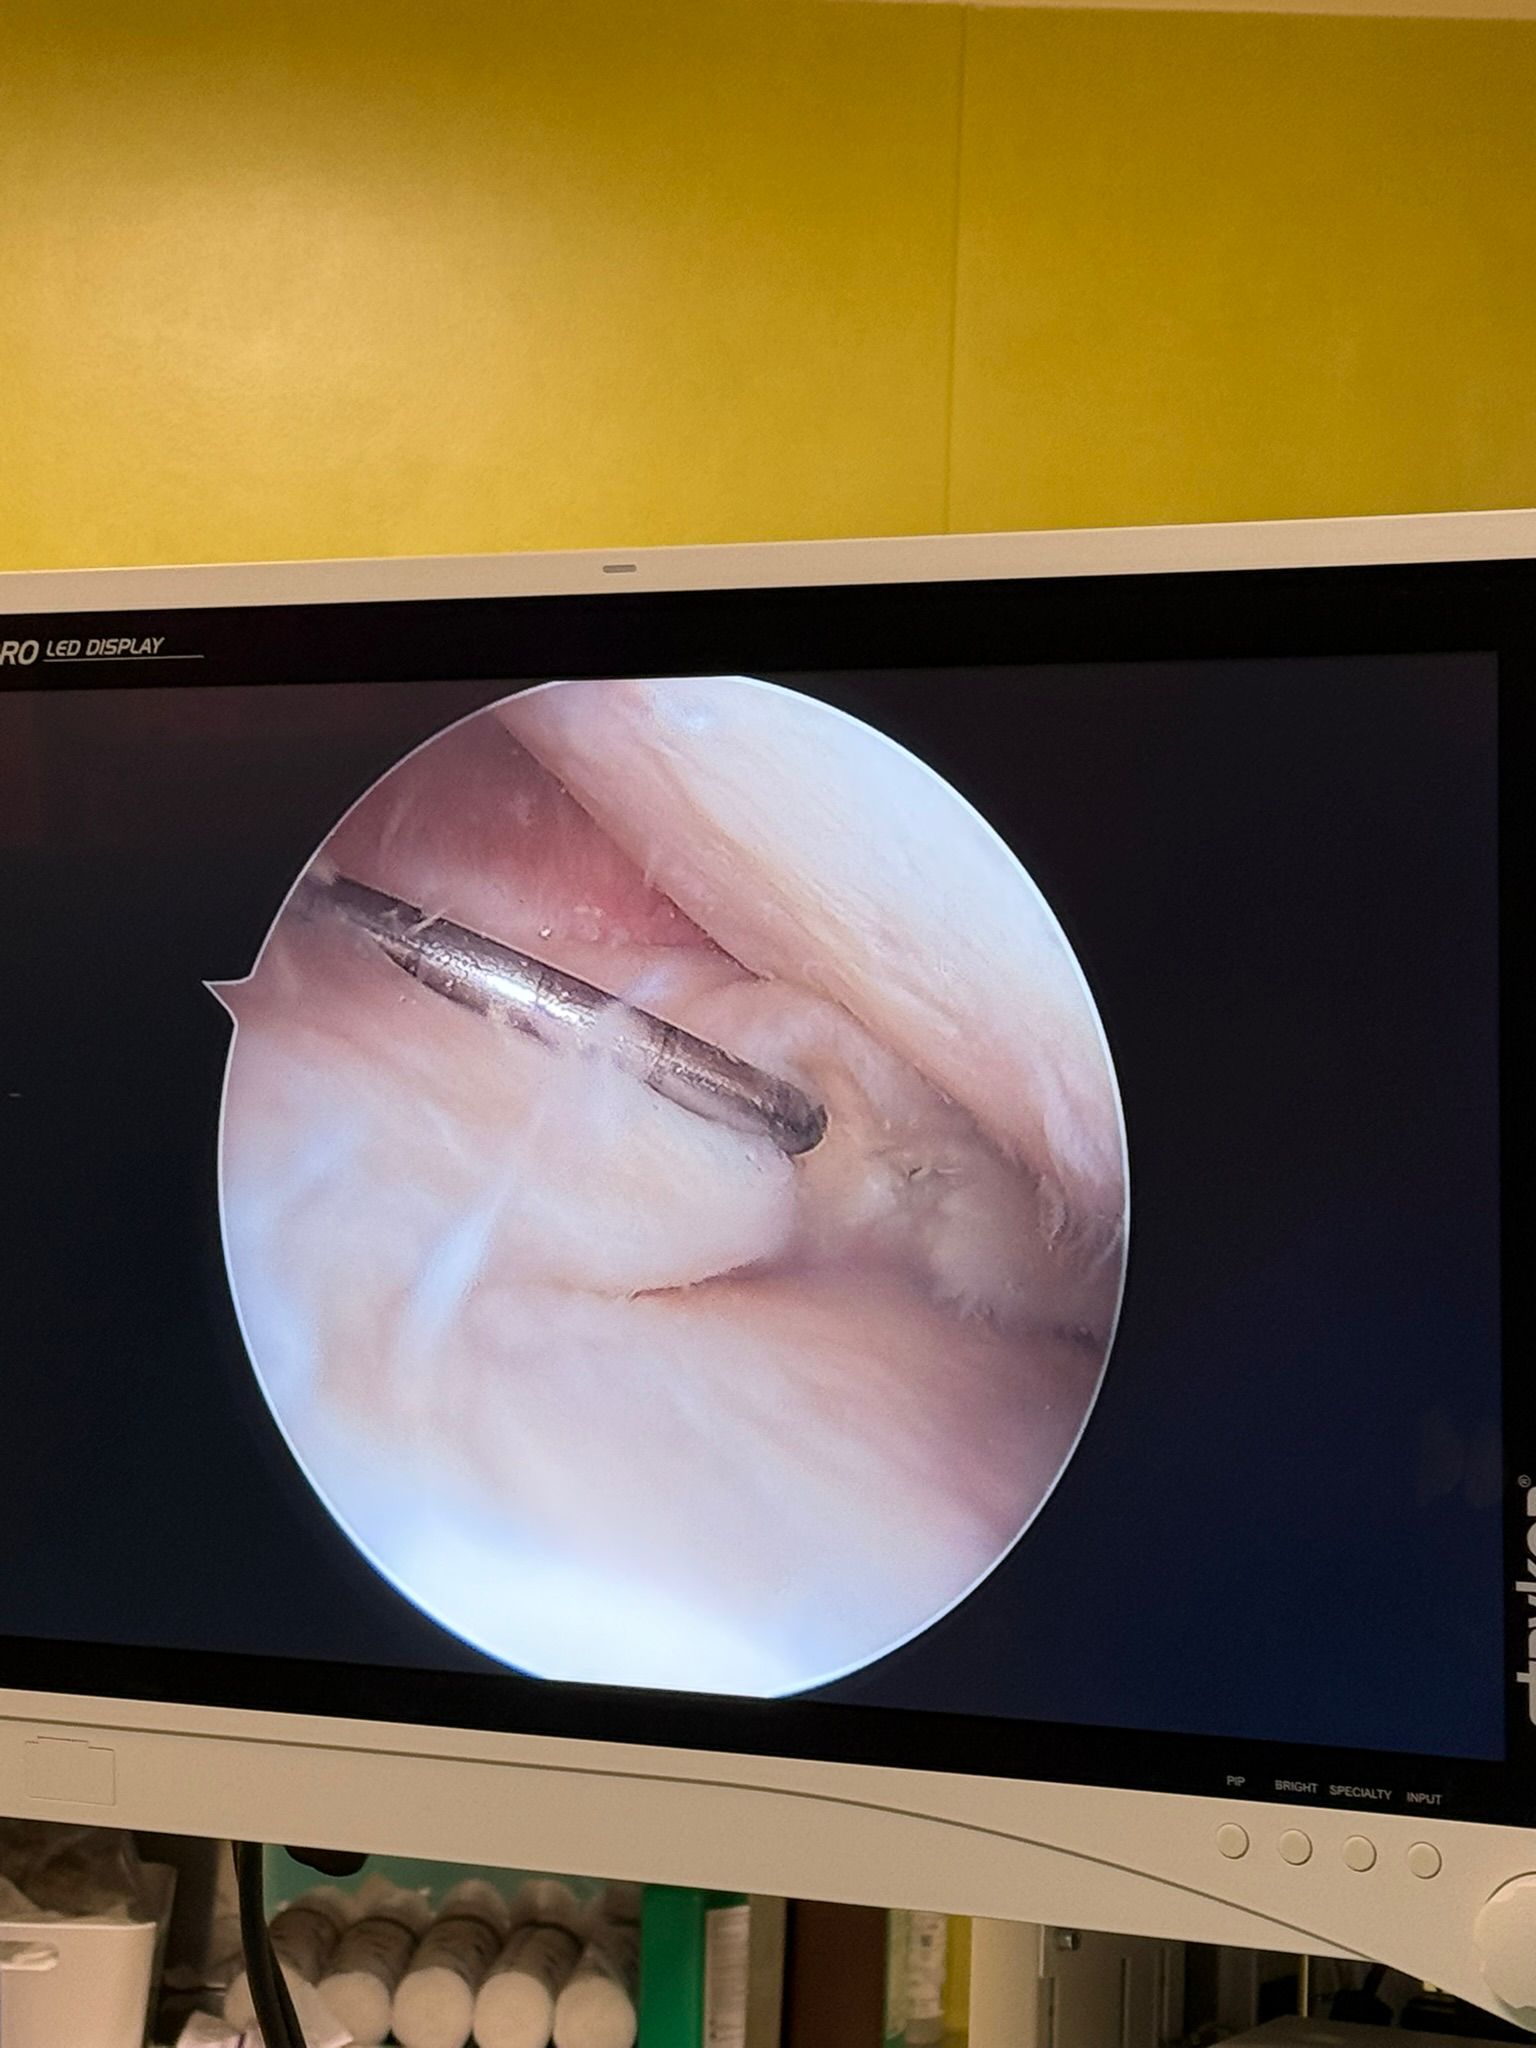

Imagini Clinice